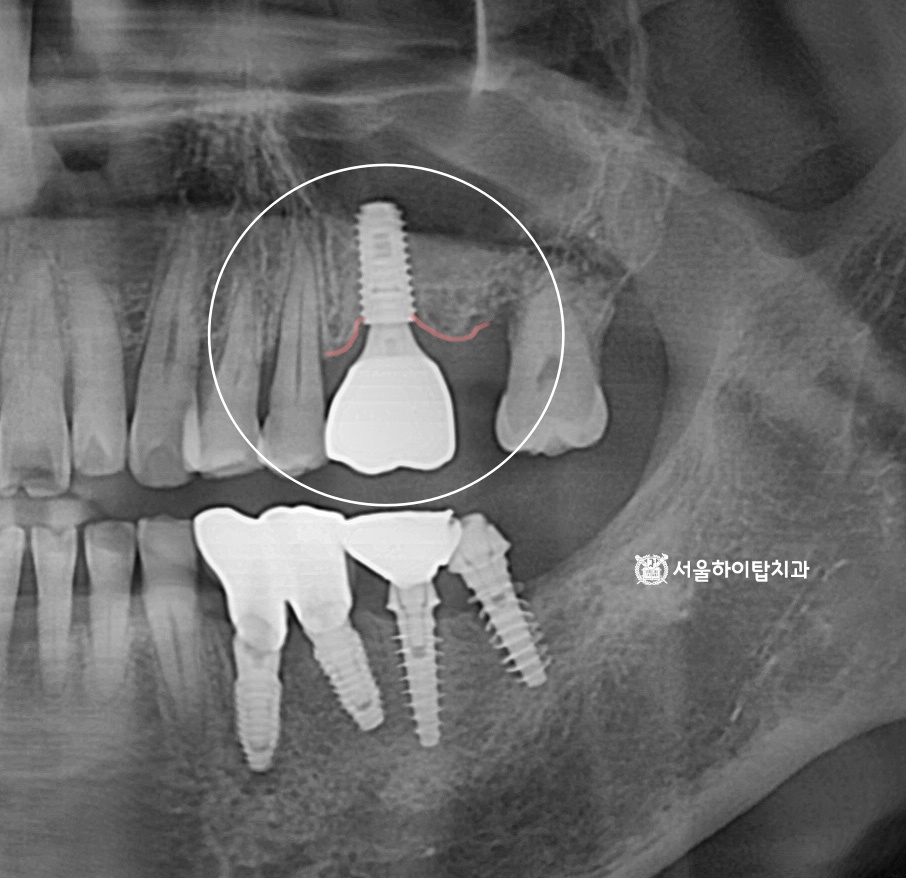

전반적으로 진행 중인 치주염과 치조골 흡수

간석역 치과 에서 임의로 표시해 둔 선을 보시면,

임플란트가 식립된 부위를 제외하고 전반적으로 치조골 흡수가 진행된 양상을 확인할 수 있습니다.

특히 어금니에만 임플란트가 식립된 모습을 볼 수 있는데,

이는 어금니가 씹는 힘을 가장 많이 받는 부위인 동시에

칫솔질이 어렵고 음식물이 잘 끼어

치주염이 가장 먼저, 그리고 가장 심하게 진행되기 쉬운 위치이기 때문입니다.

반면 앞니는 상대적으로 늦게까지 남아 있는 경우가 많아,

이처럼 어금니에만 식립된 소견이 임상에서 흔하게 관찰됩니다.

이러한 양상은 과거 또는 현재에

전반적인 치주염이 진행되었을 가능성을 시사하며,

현재 남아 있는 자연치 역시

지속적인 치주 관리와 정기적인 검진이 필요한 상태임을 의미합니다.